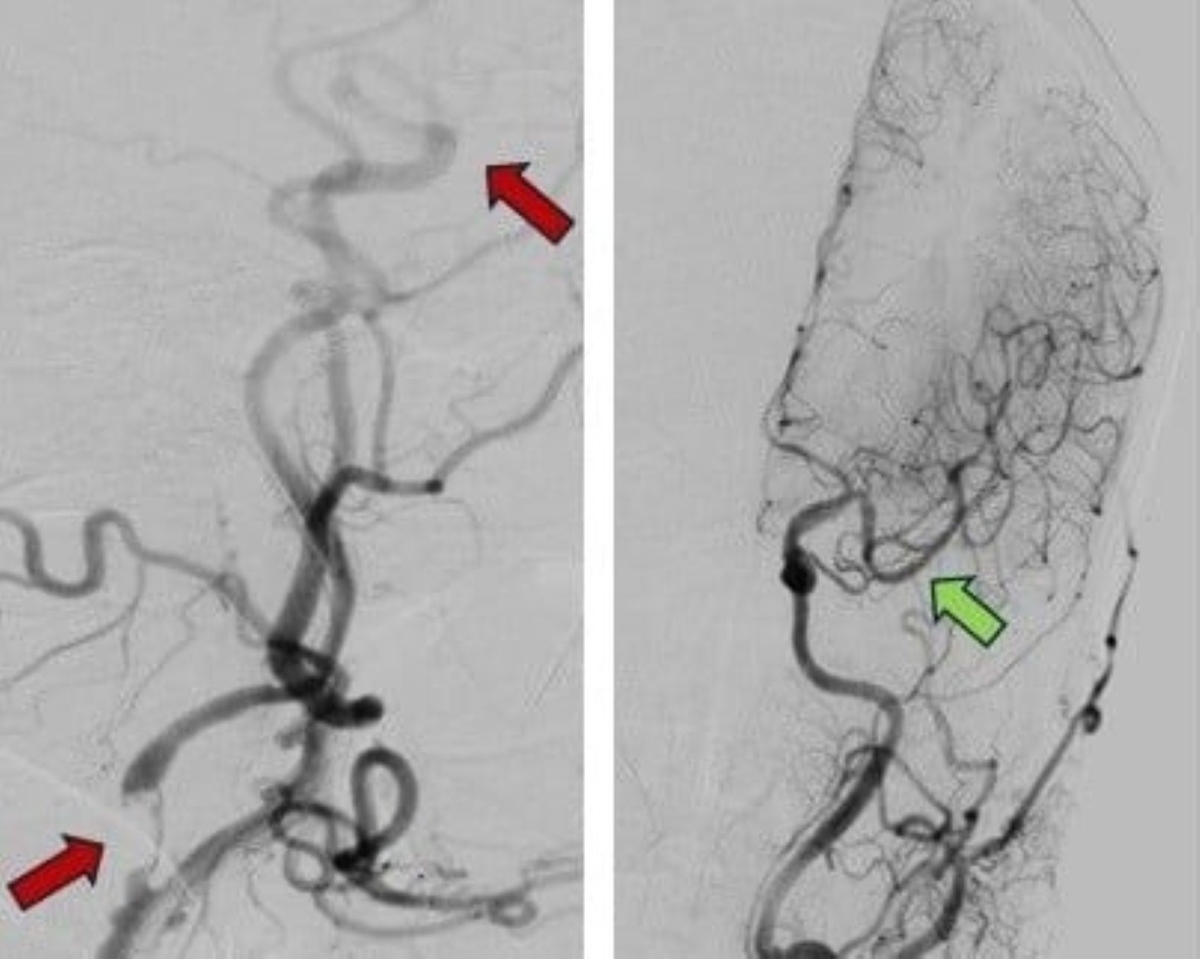

Theo kết quả chụp CT-scan, bệnh nhân bị tắc động mạch cảnh trong và động mạch não giữa bên trái – hai nhánh chính nuôi dưỡng phần lớn bán cầu não. PGS.TS.BS. Nguyễn Huy Thắng, Trưởng khoa Bệnh lý Mạch máu não, cho biết: “Người bệnh đã vượt qua thời gian có thể dùng thuốc tiêu sợi huyết, trong khi tắc mạch máu lớn khiến não thiếu máu nghiêm trọng. Cơ hội duy nhất để cứu người bệnh là can thiệp lấy huyết khối”.

Từ kinh nghiệm và kỹ thuật can thiệp hiện đại đã triển khai tại bệnh viện, các bác sĩ quyết định thực hiện thủ thuật lấy huyết khối trong cửa sổ điều trị mở rộng đến 24 giờ. Sau 55 phút thao tác căng thẳng, các bác sĩ đã lấy ra cục huyết khối, dòng máu não tái thông hoàn toàn, giúp não được tái tưới máu.

Theo đó, những bệnh nhân đột quỵ đến sau 6 giờ đều được chụp CT hoặc MRI, rồi hình ảnh chụp được đưa vào phần mềm RAPID để tự động phân tích trong 30 giây đến 2 phút. Phần mềm này giúp xác định vùng não hoại tử, vùng tranh tối tranh sáng - tức vùng não chưa hoại tử hoàn toàn, vẫn còn khả năng phục hồi nếu được tái thông mạch máu kịp thời.

Ngoài ra, RAPID còn giúp bác sĩ đánh giá nhanh mức độ tuần hoàn bàng hệ, vị trí tổn thương mạch máu, từ đó đưa ra kế hoạch can thiệp chính xác hơn. Sau gần 5 năm áp dụng, phần mềm RAPID tại Bệnh viện Nhân dân 115 đã hỗ trợ chẩn đoán cho hơn 5.000 bệnh nhân.